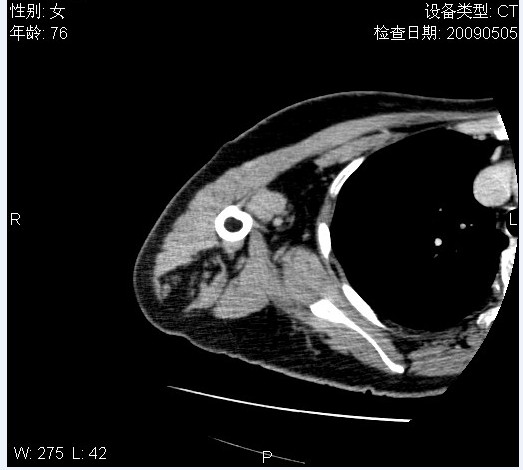

标题: CT19811:女,76岁,右上臂肿物1个月 [打印本页]

标题: CT19811:女,76岁,右上臂肿物1个月

使用了造影剂,可惜效果不太好

右肱骨上段软组织内见梭形低密度影,边界清楚,最长径约54mm.

病理结果:脂肪瘤。术中见肱骨骨膜受侵,有出血,量不详。

当时诊断意见:右肩三角肌内蔓状血管瘤(先天性动静脉瘘)。

本人对病理结果有个疑问:单纯的脂肪瘤内为什么有条状软组织影,那应该脂肪肉瘤才对啊?

该病例增强效果欠佳,由于经验欠缺,我们注射对比剂是由下肢足背静脉给药。注速2.0。虽然如此,但我们可以看到肿块内部条状软组织影是强化的,而且是连续的,并可见供血动脉是由腋动脉的其中一支即肩胛下动脉分出。从这些征象我们可以得出诊断:蔓状务血管瘤。

可病理偏偏为脂肪瘤,我怀疑取材有问题。因为蔓状血管瘤异常扩张的静脉外周是脂肪成分,它可以侵犯肌组织及骨骼。当取材于外周,那当然是脂肪瘤。此时我认为临床的最终诊断不应单从病理出发,应该综合考虑。